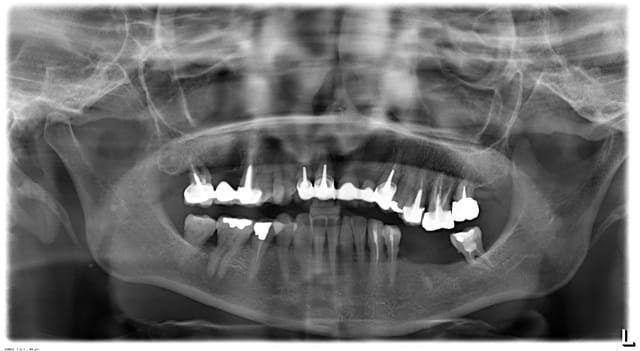

Le cas est le suivant mise en place d’un implant en place de 35. La patiente n’a pas voulu que je lui retire la racine de la 36, mais 26,27 et 38 l’ont été.

L’épaisseur de la crête est moyenne.sur la pano la distance entre le rebord osseux et le nerf mandibulaire est d’environ 14mm.

Je commande deux implants : un 4.2X12 et un 4.2X10 KONTACT de chez BIOTECH

La hauteur de racine de 34 dans l’os est d’environ 8 mm sur la pano. Cette même hauteur est mesurée à la rétro alvéolaire à 10 mm. J’en conclus (par une règle de 3) que la hauteur crête nerf mandibulaire est de 15mm. (Je n’avais pas bien repérer le nerf et n’ai pas fait le calcul directement sur la rétro)

Je suis de nature très prudent, je fore à 12mm. Radio de contrôle, je suis tangent au canal dentaire. Le Kontact doit être mis en sous crestal, même avec le 4.2X10 je ne veux pas faire prendre de risque à ma patiente. Je décide donc de poser un smilea conic à 4.4X10, que je pourrai poser en juxta.

Pano h7svml - Eugenol